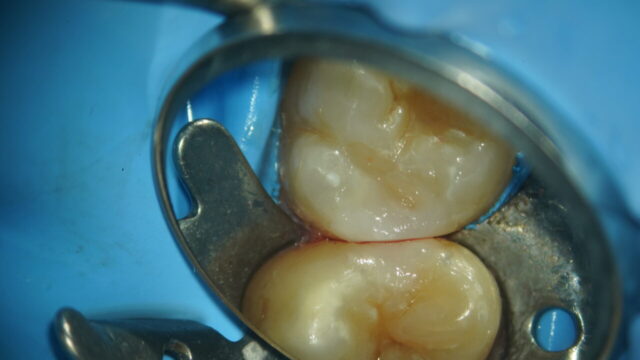

Before

詳細を見る症状 染みたりはないが問題がある歯は全て治したい 治療方法 マイクロスコープで見たところ歯の咬合面(噛む面)にれっこうう蝕という歯の溝に沿ってできてる虫歯がありました。

この歯には前にも治療した痕跡のプラスチックが詰まっていました。

過去治療している歯なので虫歯の取り残しや中に虫歯が広がっているかもと考えられ虫歯を削っていきますが、中に虫歯はなく、プラスチックも外さないで大丈夫との判断でれっこうう蝕のみ削ってダイレクトボンディングで詰めていきました。

噛む面には凸凹と溝がありますよね!真っ白なプラスチックで詰めると自然な歯をは言えないですよね。

自然な歯を作る為に溝を作ったりします!お絵描きですね。自然に自然にと歯を作ります。

ビフォーアフターの写真で自然な歯を見てください。アフターの写真の赤い点は噛み合わせを確認する為にカチカチ噛んでもらった赤い紙の色が写っています。

他にもたくさんダイレクトボンディングの症例を上げております。費用 精密虫歯治療 3.3万円

ダイレクトボンディング 2.2万円